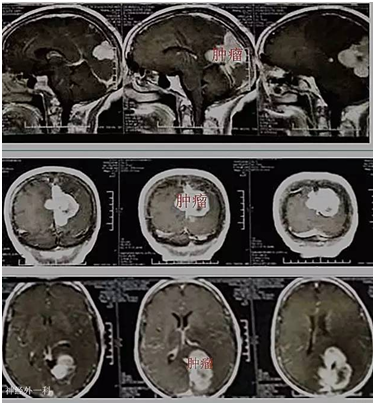

黄奶奶,72岁,因“视物模糊3个月,右侧肢体乏力半个月”入院。3个月前老奶奶无明显诱因下,出现左眼视物模糊,近半个月来出现右侧肢体乏力伴行走不稳,当地医院颅脑MR检查示:左侧枕叶镰窦旁占位性病变,门诊拟“左侧枕叶镰窦旁脑膜瘤”收入我院。入院视力1米数指。入院后完善相关检查,在全麻下行左侧枕叶镰窦旁脑膜瘤切除,手术后恢复良好,老奶奶视物较前改善,能下地行走。

大脑镰旁脑膜瘤生长在大脑半球纵裂中,往往位置较深。肿瘤较小时一般不出现临床症状,因此发病时肿瘤往往已长得较大。也有例外,如果出现肿瘤小且瘤周水肿重或者早期出现癫痫,发现时肿瘤往往比较小。以下谈谈大脑镰脑膜瘤常见症状和体征:

视野缺损。甚至失明:脑膜瘤位于大脑后部时,可以引起视野改变,常未引起病人注意。检查可发现视野缺损。肿瘤常长到巨大体积时,巨大镰旁脑膜瘤可压迫双侧枕叶距状裂,造成失明。本例患者肿瘤正好压迫皮质视感觉区,出现视力严重下降。